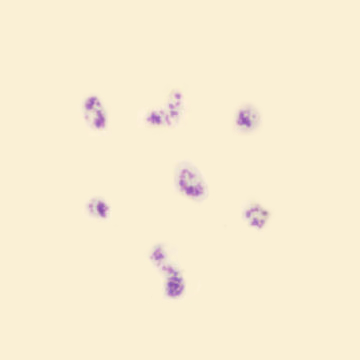

In the smear, the reticulocytosis as noted in the RET channel is readily apparent; polychrome erythrocytes are plentiful. If you look closely, you can also see some erythrocytes with howell-Jolly bodies.

Thrombocytes

The platelet count is 1065*10^9/L, which is physiological for the mouse. In humans, such values are seen almost exclusively after splenectomy or in myeloproliferative disorders, such as Chronic Myeloid Leukemia, Essential Thrombocytosis or Primary Myelofibrosis. Additionally, the marked variation in shape and size of the platelets is striking.

Neutrophils are relatively small, hypogranular and show slight hypersegmentation. Some neutrophils have an O-shaped nucleus; this morphology is considered the equivalent of the rod-core neutrophil in humans.

Mouse peripheral blood may consist largely (up to about 90%) of lymphocytes. The frequent occurrence of damaged cells is striking. Mouse lymphocytes are fragile and are easily smudged during bloodfilm preparation.